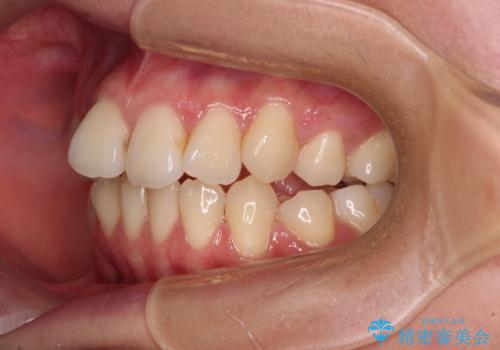

- 抜歯矯正の後戻りを気にして来院された患者様です。

舌の突出癖によるオープンバイトになっていたため、インビザラインによるマウスピース矯正をおすすめしましたが、自己管理の自信がないとのことで、ワイヤー装置による矯正治療を行うこととしました。

舌の突出癖が認められると、上下前歯の隙間を閉じることができません。

舌のトレーニングをしっかりと行っていただくことで、歯列を整えることができます。

- 矯正治療後の保定が不十分だと後戻り(元の位置に戻ろうとする動き)をします